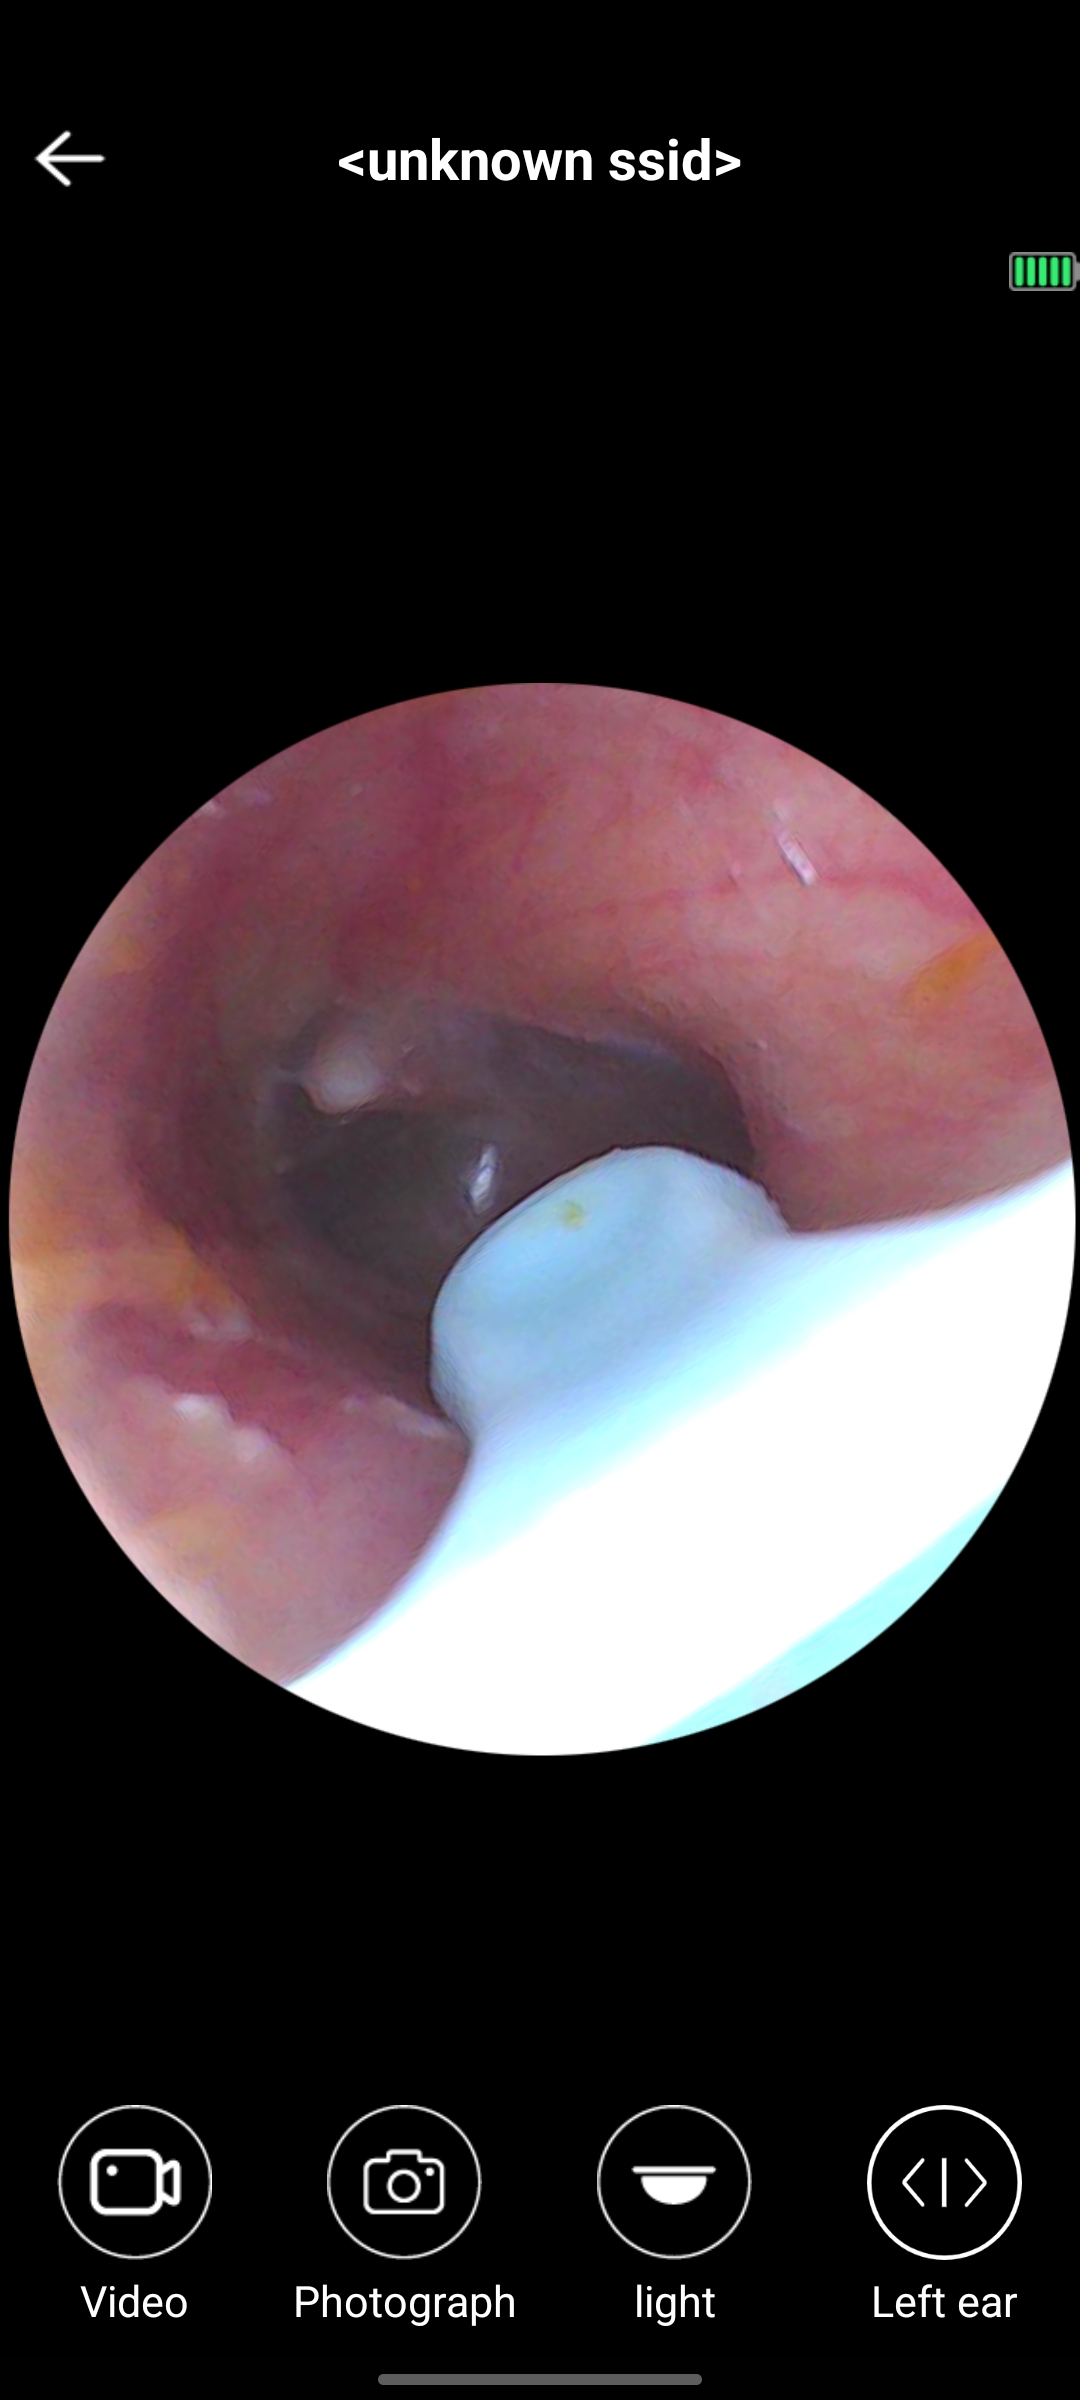

สวัสดีครับ มีจุดสีขาวในหูแบบนี้ปกติไหมครับ

มีก้อนสีขาวที่ข้างในรูหู

น้องชายมีก้อนสีขาวที่ข้างในหูค่ะ คล้ายก้อนสำลีที่อยู่ไม้แคะหู ถามก็บอกว่าไม่ได้แคะหูไม่ได้ทำอะไรติดไว้ในหู แม่พึ่งมาเห็นเมื้อกี้ ก้อนใหญ่เต็มหู แต่น้องชายบอกว่าไม่รู้สึกเหมือนมีอะไรอยู่ในหูเลย จิ้มก็ไ

สีขาวๆ ในหูที่เป็นก้อน อันตรายไหมคะ

ตอนนี้ยังได้ยินปกติ แต่ไม่กล้ายุ่งกับมันกลัวเจ็บคะ อยากทราบว่าอันตรายไหมแอบน่ากลัวนิดนึง